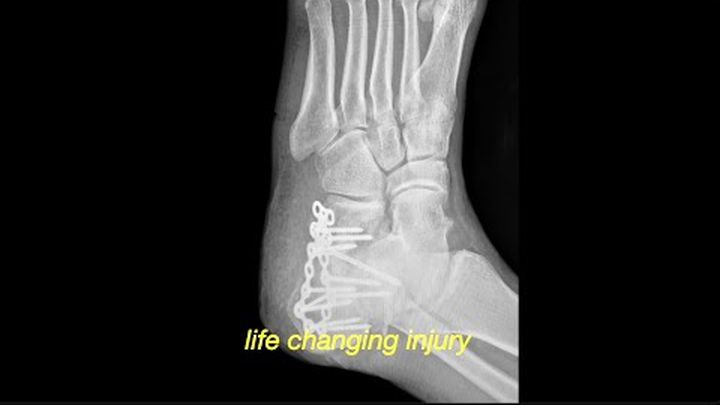

Last month, I suffered a devastating accident that shattered my heel and left me in debilitating pain and unable to work. The injury was so severe it required intensive surgery and I now face a long road to recovery. My doctor told me I’ll never walk the same again. I’ll be dealing with chronic pain and a bone fusion surgery is likely within the next 1–3 years. On top of that, my insurance had lapsed, so every medical bill has been out of pocket.